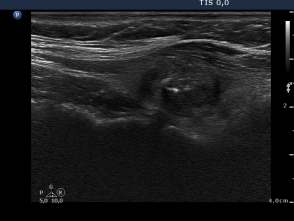

Four months before the sclerotherapy (first row of images):

Clinical presentation: a 45-year-old woman with an autonomously functioning adenoma known for 3 years was referred for evaluation. Her TSH level decreased continuously but was normal until the last checking. She had no complaints.

Palpation: a moderately firm nodule in the right lobe.

Hormonal investigation indicated euthyroidism (FT4 15.9 pM/L) with a subnormal TSH (0.19 mIU/L).

Ultrasonography: the thyroid was echonormal. There was a moderately hypoechogenic nodule in the left lobe. The lesion displayed halo sign.

Suggestion: TSH-test every six months.